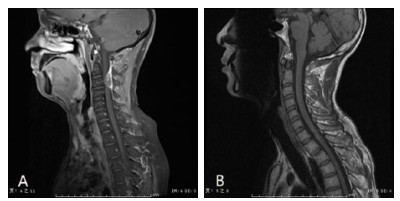

疗效评价:7例未手术患者中,除1例放弃治疗外(死亡),保守治疗2周后脊髓功能评估D级3例,E级3例。手术患者术后两周评估A级5例,C级5例,D级8例,E级4例。除1例死亡患者外,本组28例患者随访时间3~62个月,(48.7±23.1)个月。随访未手术6例患者,预后良好(评估为E级),症状完全消失,影像学检查未见复发。22例手术患者中,10例入院为A级患者中,6例恢复良好(D/E级),4例预后不佳生活不能自理(A级3例,C级1例);7例术前为C级患者随访中,基本恢复日常生活(D级2例,E级5例);而5例术前D级患者预后亦良好,随访肢体活动能力全部恢复(E级)。见表 1图 1

A:矢状位提示硬膜外占位性病变,同水平脊髓受压明显;B:术后复查见血肿清除彻底,脊髓形态恢复 图 1 典型C2节段硬膜外血肿术前术后MRI影像资料 Fig 1 MRI images of typical C2 epidural hematoma before and after surgey